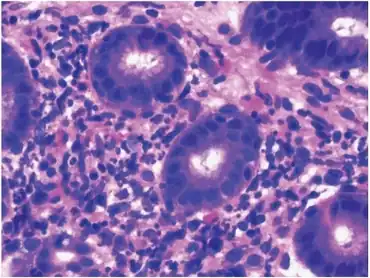

| Histopathology of HSP involvement in small bowel showing neutrophilic and eosinophilic infiltrates | |